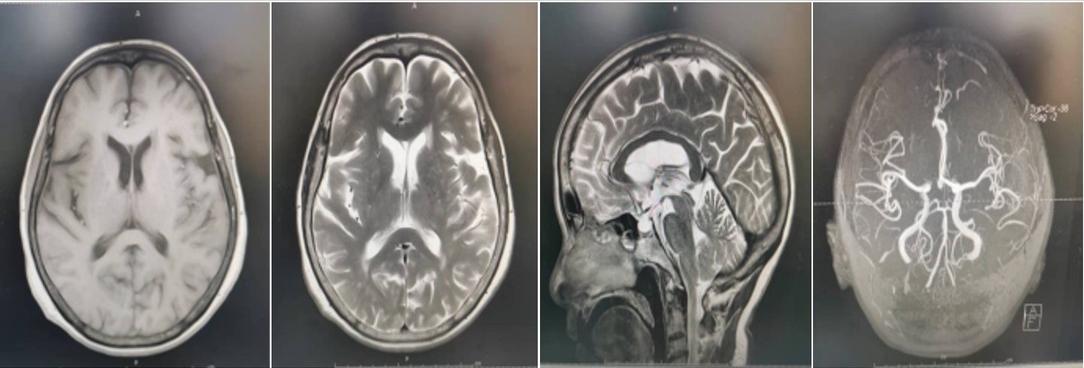

患者头颅MRI影像片

74岁的李先生,五年前出现右手活动不灵活,逐渐发展为四肢活动不灵活,僵硬,行走缓慢,辗转多家医院就诊,先后按照“脑梗死、周围神经病、帕金森病”给予相关药物治疗,步态异常无明显改善。且出现行走时起步困难,需等待数十秒可启动步伐,行动迟缓,小碎步,担心摔倒,很少外出活动,严重影响独立生活。来院后胡晓辉主任携科室全体医生详细神经系统查体,发现典型体征:面具脸,四肢肌力Ⅴ级,肌张力呈铅管样增高,慌张步态,尤其启动时呈粘滞步态,双侧病理征阴性。结合患者病史、既往治疗过程、头颅MRI及相关检查结果,诊断 “ 帕金森病冻结步态”。